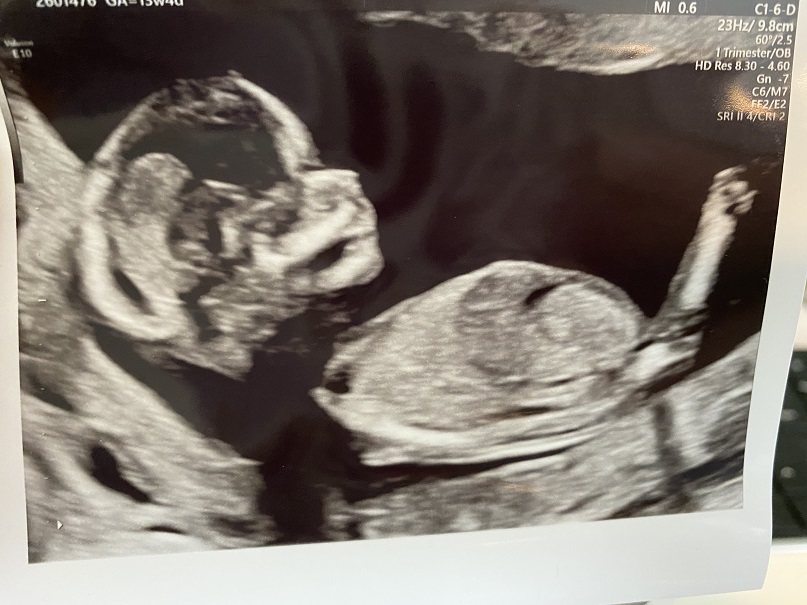

Can anyone point up where the nub is in these pics? 13w 4d NT scan

I posted these pics in a few other forums and got mostly boy leans but some girl ones as well. When I asked if they were basing their guess off of the skull shape or if they can point out the nub to me, nobody replies! Except one lady said her intuition was that it was a girl. Which doesn't give me much hope lol. Ramzi and skull theory seem to point to boy. And even though I didn't get a pic of the potty shot, it looked like a triangle down there so I'm thinking this is a boy. Which will make our 4th boy and last child so I'm feeling a bit gutted and wishing I would have pushed a little harder to convince my husband to go high-tech. I just took my NIPT so we'll find out soon enough. Any guesses are appreciated either way! Let me know if you see a nub!

Attachment 42961Attachment 42962